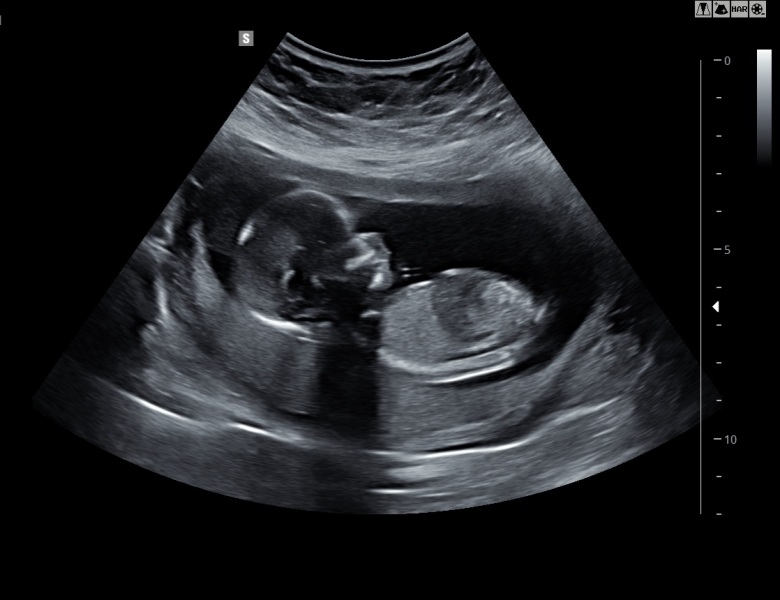

Oh our baby is perfect 🥰❤️ started booing my eyes out!! They've put our new date at 13+1 so 3 days earlier. Feel like a huge weight has been lifted. We've got a right little wriggler

@Sb86 been refreshing all afternoon! Yay!! So we are still exactly the same! My new dates make me 13 + 1 today and due on 8th! So happy for you xxx

Here is my little bub 🥰❤️ I'm so in love!

@Sb86 amazing scan photo!! Its amazing how much you can love someone so tiny and that you've never even met 😍xx

@TTCRainbow the scan photos we had printed off weren't as good as this, I snook a photo of the screen when she had her back turned. Unsure why she didn't choose to print this one off as it's amazing 😍 I can't stop looking at it. I've got children already but I'll never get over how something so tiny is so perfectly formed and in such a short space of time. It truly is a miracle ❤️ xx